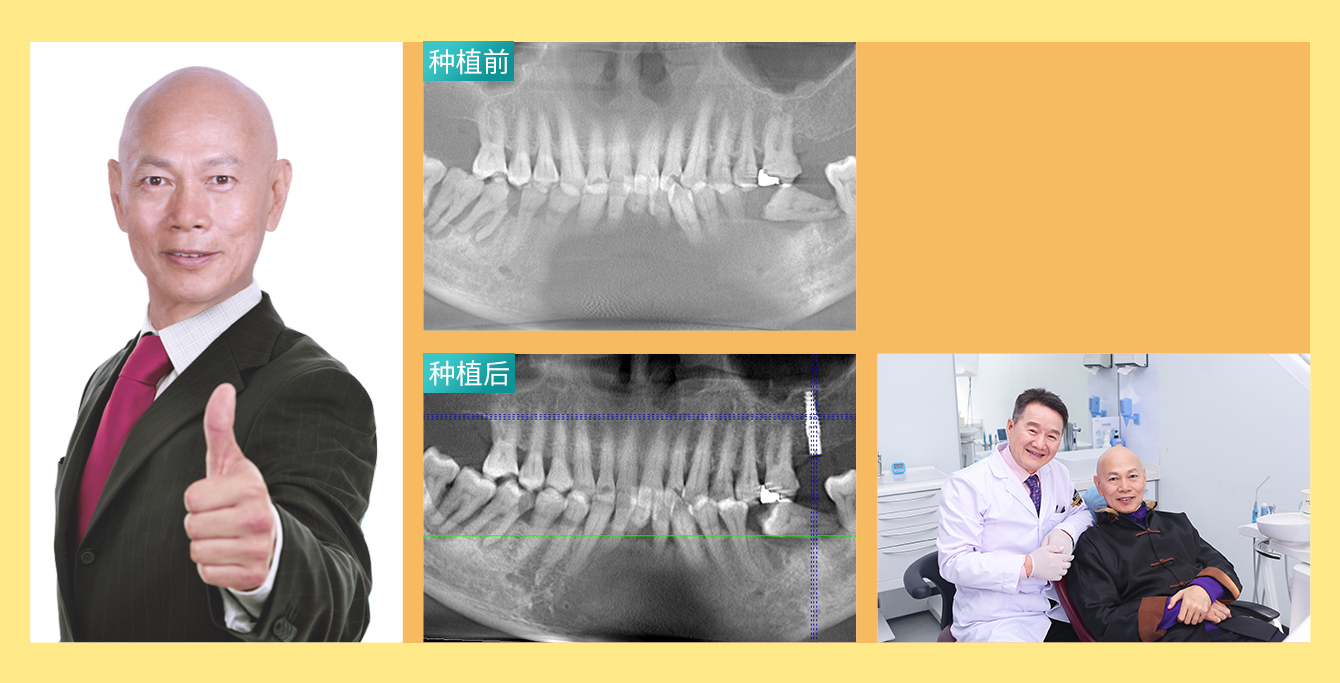

• 种牙人:香港著名影星程东

年龄:59岁

主诉:多颗牙缺失

种牙方式:智能数字化精确种植牙

代表作:《赌侠》 、《整蛊专家》